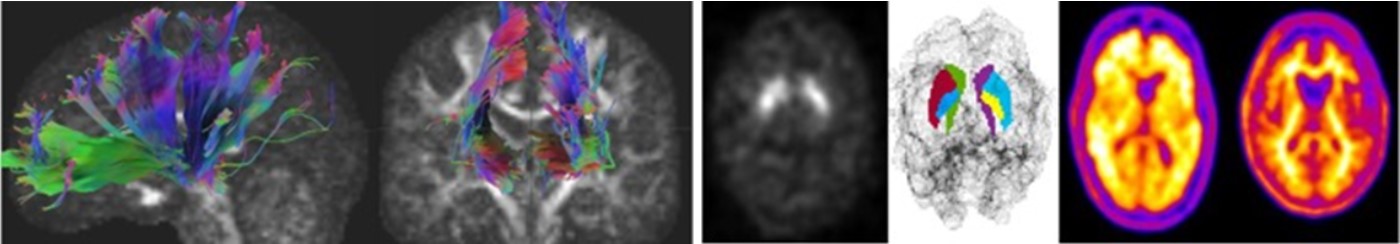

分子イメージングは、体内で起こっていることを分子や細胞レベルで詳細に描写する画像診断手法の一種です。X線、コンピュータ断層撮影(CT)、超音波などの他の画像診断では、身体構造の画像を得ることができますが、分子イメージングでは、身体がどのように機能しているかを確認し、化学的および生物学的過程を測定することができます。分子イメージングには、MRIや核医学といった画像診断手法が含まれ、疾患を初期段階で捉えることや、腫瘍の正確な位置の特定などに役立ちます。分子イメージング学分野では、これらのイメージング手法の開発・評価だけでなく、画像解析による新たな診断指標の開発や予後との関連を明らかにすることを目標としています。

磁気共鳴イメージング(MRI)は、組織内の水分子の状態や挙動に応じたコントラストを画像化することができ、脳のような軟部組織の詳細な画像を得ることができます。MRIを用いて神経疾患(アルツハイマー病、パーキンソン病等)、精神疾患における新たな画像バイオマーカーの開発を行うとともに、脳機能および脳構造を非侵襲的に評価するための解析手法や、評価精度の向上を目的とした画像処理技術の開発に取り組んでいます。

核医学に関する研究(白川、辻本)